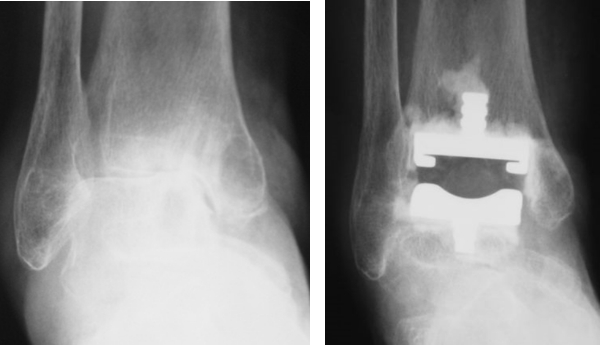

OA、RAの足関節障害には人工足関節置換術(total ankle arthroplasty: TAA)(図9)や関節固定術を行います。TAAは距踵病変がなく、比較的変形の少ない例に施行され、可動性を保つことができます。固定術は高度変形にも適応があり、関節の安定化が期待できます(図10)。RAは距踵関節にも破壊が生じやすいため、距腿関節と距踵関節(Tibio-talo-calcaneal: TTC)を同時に逆行性髄内釘で固定することもあります(図11)。

図9:人工足関節置換術

図10 足関節固定術

図11 RAの足関節障害に対するTTC固定術